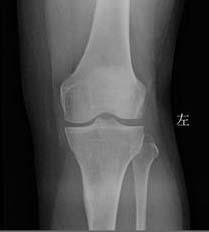

(图:患者治疗风湿后左膝关节X线表现)

第二个疗程治疗结束后,马友文主任按压其膝关节时,无疼痛感,关节肿胀消失,膝关节活动能力恢复,下蹲、屈伸活动均不受限。马友文主任检查后诊断程女士风湿性关节炎病症有效消除恢复健康。

程女士第三次来院复诊时,HD—热层析检测系统检测显示,膝关节炎性症状消失,全身关节无疼痛感。类风湿因子18IU/ml,抗链球菌溶血素151u/ml,血沉14.6mm/h,超敏C反应蛋白3.9mg/L,检查结果显示均为正常值。